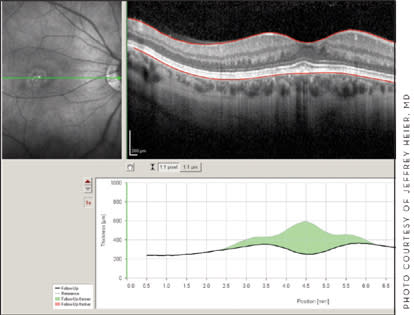

Figure 1. Marked regression of non-AMD choroidal neovascularization in a 37-year-old patient (Spectralis HRA+OCT).

The Spectralis FA + OCT allows the clinician to perform different functions at the same time, such as fluorescein angiography in conjunction with OCT or red-free or infrared images in conjunction with the OCT. "Auto-fluorescence is becoming more and more important to us as we look at dry macular degeneration," Dr. Heier says. He often obtains an autofluorescence and then a spectral domain scan through the same area. "We're picking up subtle changes in the RPE. We're picking up patterns of degeneration that may in the future help to be predictive of either disease progression or treatment response or other findings along those lines," Dr. Heier says.

Recent and upcoming Spectralis advances are focusing on retinal segmentation, system reports, and quantification software for autofluorescence images, Dr. Heier says. Major advances have been made in glaucoma analysis in measurements of retinal nerve fiber layer thickness and optic nerve changes, as well as in reproducibility.

All SD-OCT devices have different advantages, Dr. Heier says, but he believes the Spectralis OCT has superior image quality and outstanding eye tracking and reproducibility, which he says are important in monitoring patients from visit to visit.

The dual-scanning mode coupled with reference scanning, allows clinicians to be very confident of the pathology and subsequent progression or responses to treatment, he says. "You're able on 1 scan to ensure that you are focused on the region in question and on the other scan evaluate with high-resolution OCT abnormal findings or changes in anatomy."